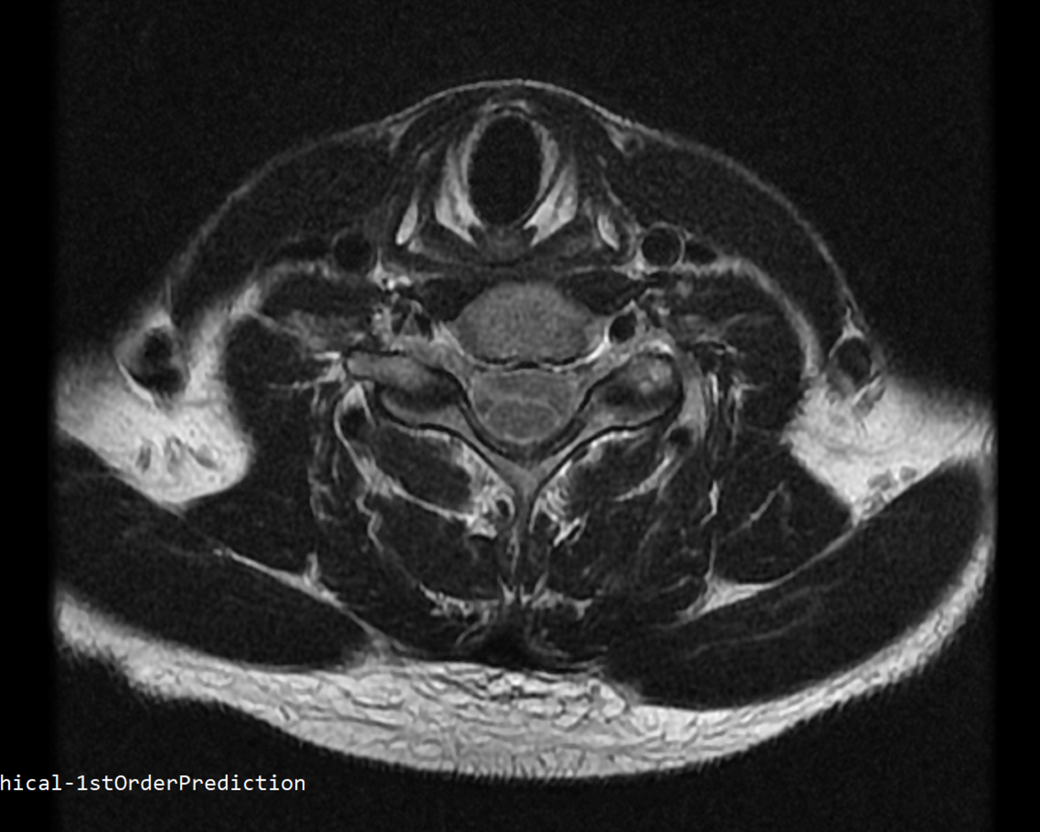

안녕하세요 목 경추 상단부터 순서대로 mri 촬영인데요

전체적으로 봐주시면 감사하겠습니다

하단8번 신경쪽도 나오는건지.. 봐주시면 감사하겠습니다

• 4번 째 사진